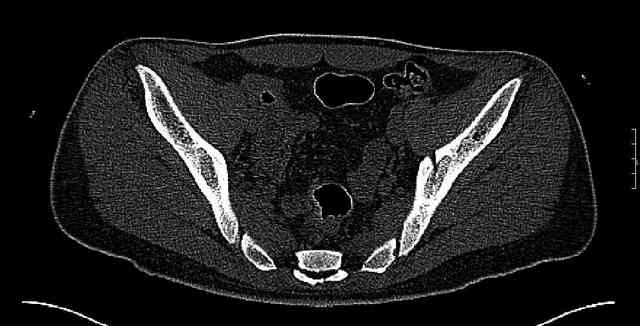

The last two images from the 3-D CT scan certainly makes the fracture look worse than the plan radiographs.

Some more images. Does it help to guess which part of the acetabulum is displaced?

Normal appearing SI joints and a healed posterior column limb... my bet's on caudal segment displacement.